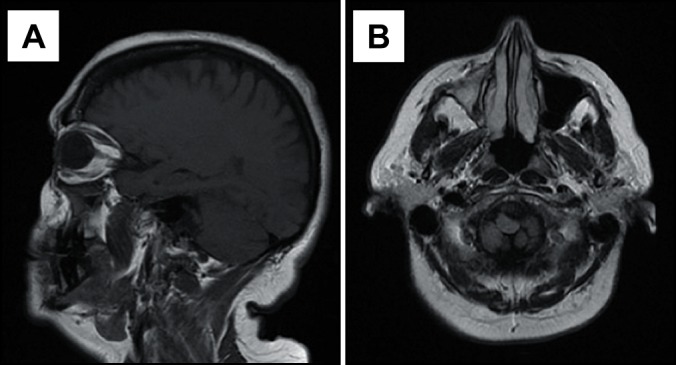

背景:磁共振成像被认为是诊断炎症性上颌窦疾病的较好影像学检查,可以提供精确的鼻窦特征。磁共振弥散加权成像与表观弥散系数是互补的磁共振成像工具,可用于鼻窦疾病的鉴别。本文报告3例炎症性上颌窦疾病结合弥散加权磁共振成像特征的影像学表现。此外,文献综述考虑使用扩散加权磁共振成像在炎性病变提供。方法:病例报告:存在气液水平,粘膜增厚和粘液潴留囊肿。常规磁共振成像和表观扩散系数(ADC)图,显示了ADC值。在文献综述中,详细介绍了考虑炎性病变的研究,以及研究者建立的ADC值。结果:气液水平、粘膜增厚和粘液潴留囊肿的ADC值分别为:1.99 x 10-3 mm2/s;1.83 × 10-3 mm2/s;2.05 × 10-3 mm2/s。结论:观察到本报告所描述的炎性病变的表观扩散系数值不同,表观扩散系数可用于鉴别这些上颌窦病变。进一步的大样本调查考虑明显的扩散系数值集中在炎性病变建议。缺乏考虑使用弥散加权磁共振成像诊断炎症性疾病的研究是文献综述的主要限制。

ABSTRACT Background Magnetic resonance imaging is considered a preferable imaging examination in the diagnosis of inflammatory maxillary sinus disease and can provide precise sinonasal characterization. Diffusion-weighted magnetic resonance imaging and apparent diffusion coefficient are complementary magnetic resonance imaging tools that can be applied to the differentiation of sinus diseases. In this report, 3 cases of inflammatory maxillary sinus diseases imaging findings considering diffusion-weighted magnetic resonance imaging features were described. Additionally, a literature review considering the use of diffusion-weighted magnetic resonance imaging in inflammatory lesions is provided. Methods The cases reported were: presence of air-fluid levels, mucosal thickening and a mucous retention cyst. Conventional magnetic resonance imaging and apparent diffusion coefficient (ADC) maps, with ADC values were demonstrated. In the literature review, the studies considering inflammatory lesions were detailed, as well as ADC values established by investigators. Results ADC values for presence of air-fluid levels, mucosal thickening and mucous retention cyst were respectively: 1.99 x 10-3 mm2/s; 1.83 x 10-3 mm2/s; 2.05 x 10-3 mm2/s. Conclusions It was observed that apparent diffusion coefficient values from the inflammatory lesions described in this report were different and apparent diffusion coefficient may be useful in the differentiation of these maxillary sinus alterations. Further larger sample investigations considering apparent diffusion coefficient values focusing in inflammatory lesions are recommended. The lack of studies considering the use of diffusion-weighted magnetic resonance imaging on inflammatory diseases diagnostic was the major limitation to the literature review.